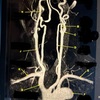

What kind of MR image ? • A. MR spectroscopy • B. MRA Circle of Willis • C. MRV intracranial circulation • D. MRA extracranial circulation E. MRA intracranial circulation

D. MRA extracranial circulation

1 Right Internal Carotid Artery 2 Right Common Carotid Artery 3 Left External Carotid Artery 4 Left Common Carotid Bifurcation 5 Right Subclavian Artery 6 Left Subclavian Artery 7 Thoracic aorta 8 Brachiocephalic (Innominate) Artery 9 Left Vertebral Artery 10 Basilar (V-B) Junction

A Basilar (V-B) Junction B left external carotid artery C Left Common Carotid Bifurcation D Left Vertebral Artery E Left Subclavian Artery F thoracic aorta G Brachiocephalic (Innominate) Artery H Right Subclavian Artery J Right Common carotid artery K Right Internal Carotid Artery